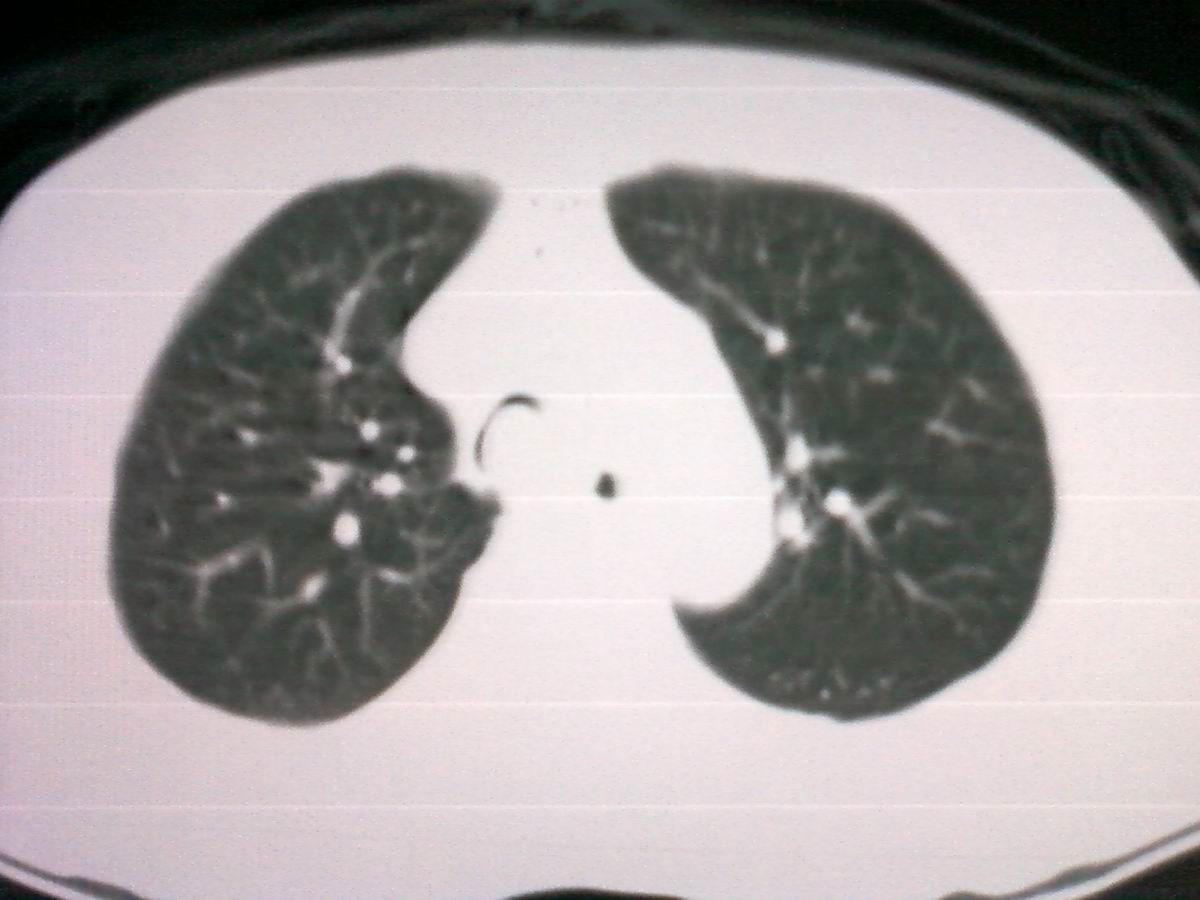

标题: CT25801:患者男性,65岁,临床提示双肺可闻及广泛罗音,看 [打印本页]

标题: CT25801:患者男性,65岁,临床提示双肺可闻及广泛罗音,看

仅见肺纹理影增重 纵膈淋巴结钙化

气管后部见半圆形软组织密度病灶,考虑占位,建议气管镜除外鳞癌。

气管上段的肿瘤多为良性乳头状瘤,气管下段的肿瘤多为鳞癌,气管中段的良恶性各占一半。本例位于气管下段,先按恶性处理。不过纤支镜是免不了的。